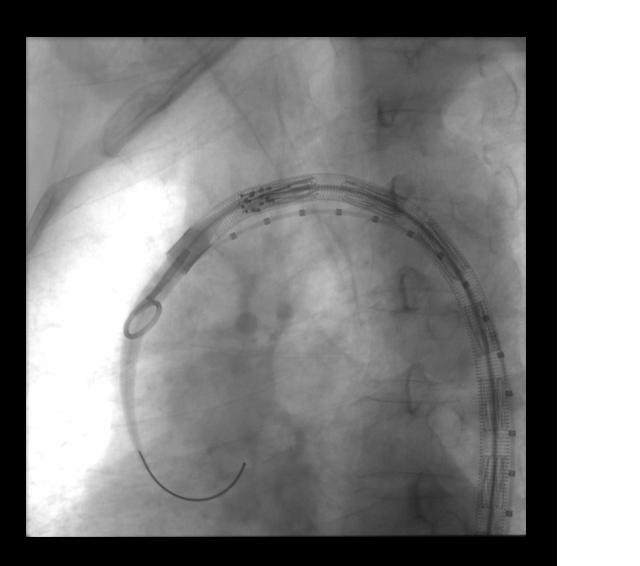

EVAR